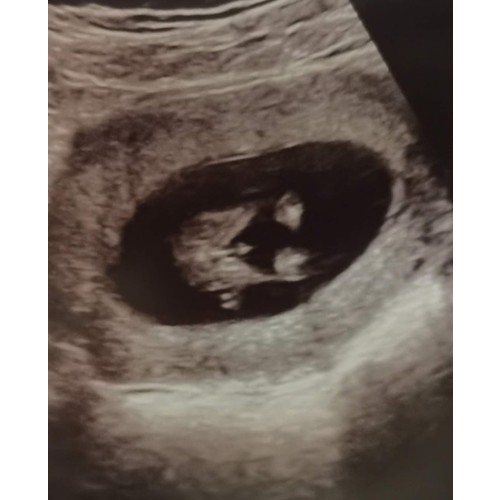

Ons jochie met exact 13 weken. Was niet te missen.

(voordat er mensen roepen: 'waarom doe je zo vroeg een geslachtsecho' ; dit was geen geslachtsecho maar de zoveelste echo vanwege bloedingen, de echoscopiste wilde er even een positief en fijn momentje van maken en showde ons toen dit haha)

Zo daar is geen twijfel mogelijk🙈

Je ziet 3 streepjes.. dat zijn de schaamlippen met in t midden de clitoris. Kan echt niet missen.

Ik zeg meisje. Maar het lijkt ook een beetje alsof de foto een beetje bewogen is